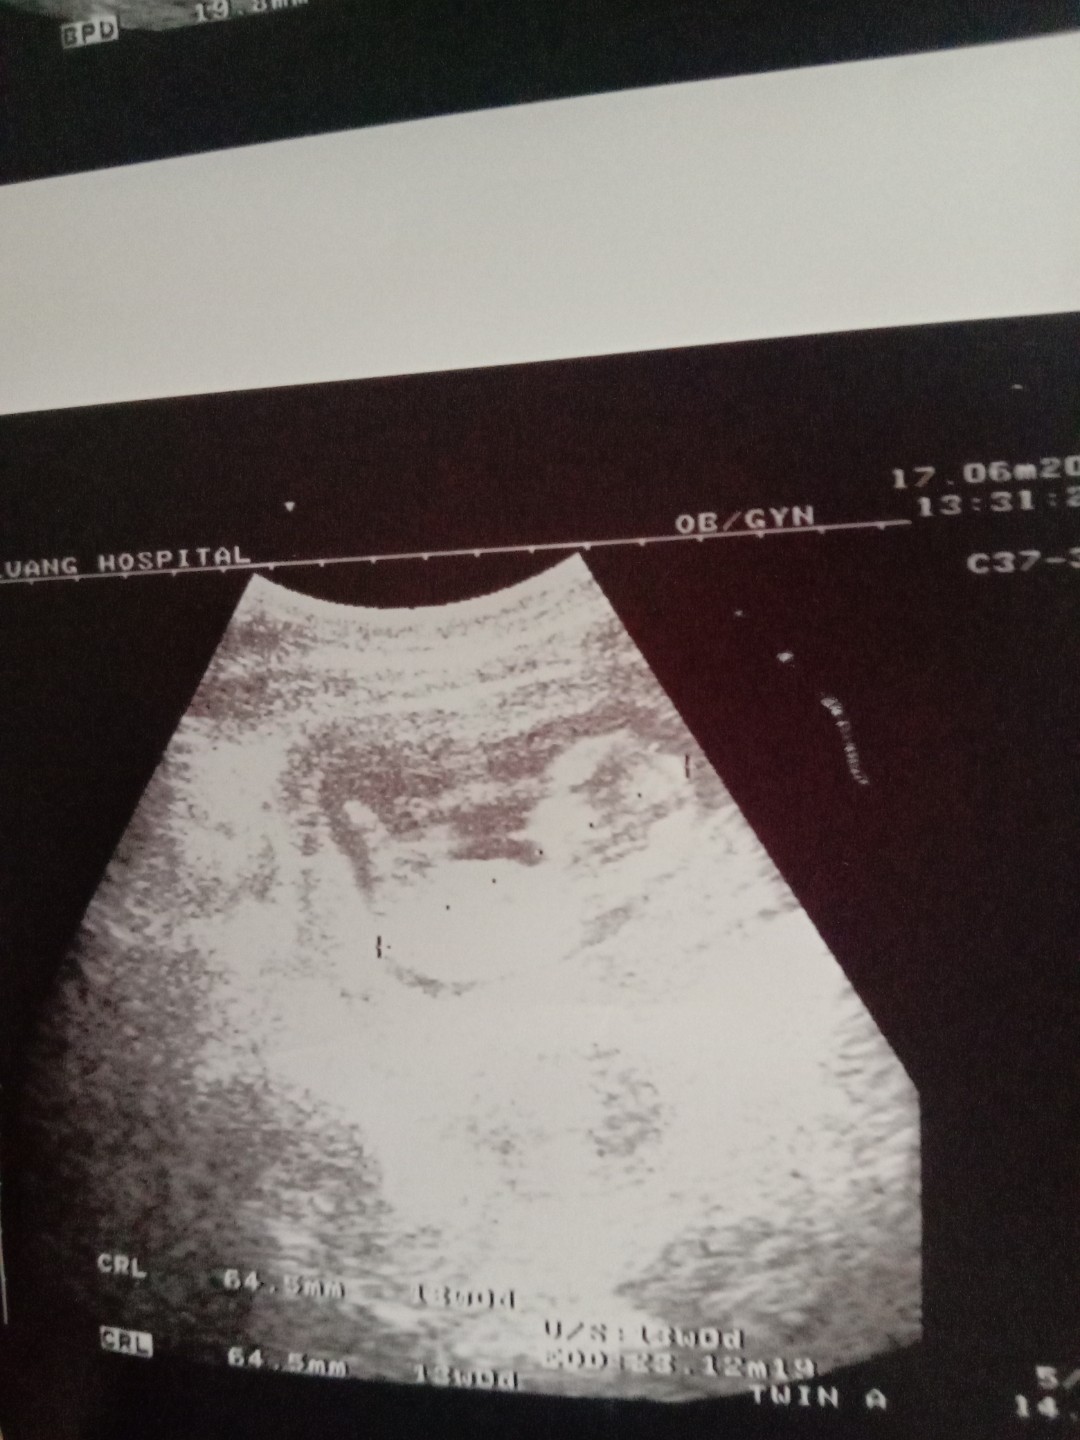

13wคะ